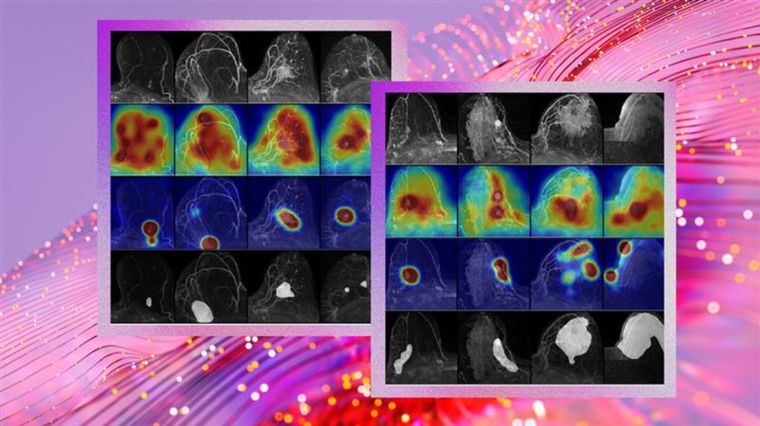

Microsoft y su equipo desarrollaron un modelo denominado FCDD (Fully Convolutional Data Description), que se enfoca en identificar anomalías en lugar de intentar clasificar todos los tipos posibles de cáncer. A través de una base de datos con más de 9.700 resonancias mamarias, el modelo fue probado en entornos reales con resultados prometedores.

- Visualización explicativa, gracias a mapas de calor que indican zonas sospechosas, con una precisión del 92 % en comparación con las observaciones de radiólogos expertos.

La herramienta de inteligencia artificial genera mapas de calor que indican con claridad las áreas sospechosas.